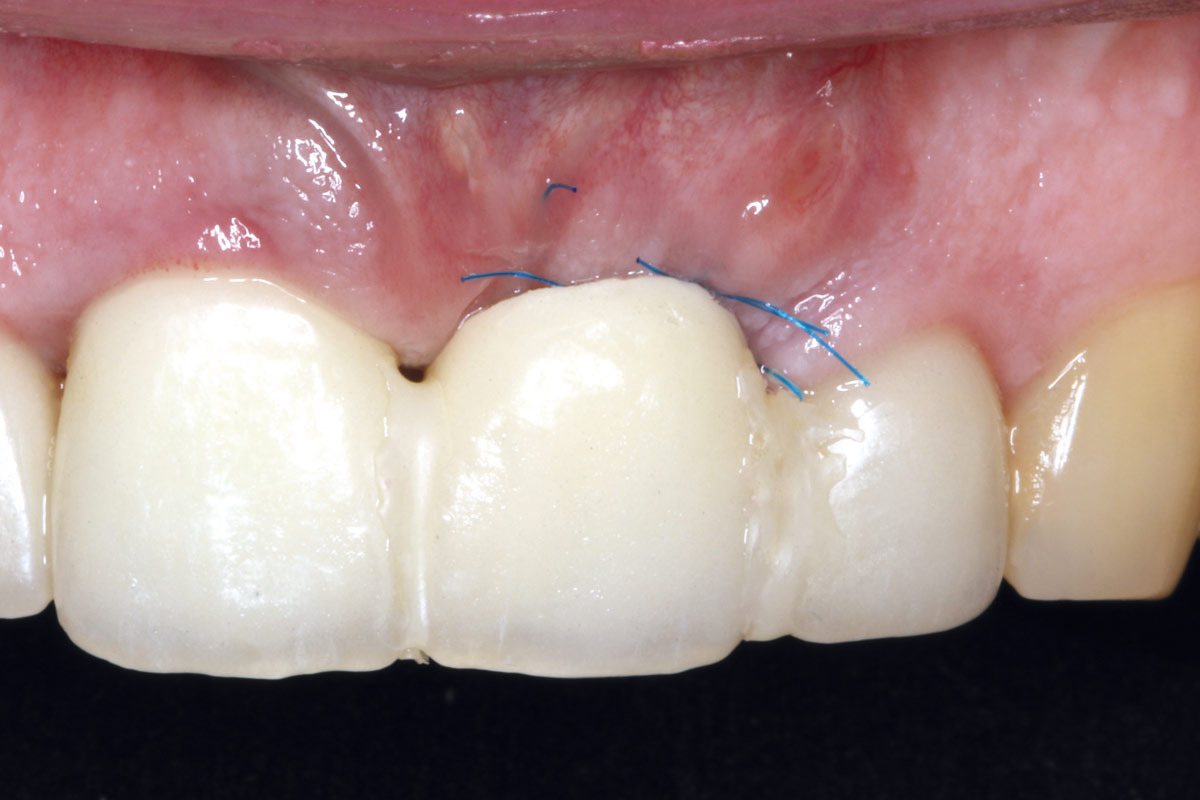

06/10 - Suturing; mucoderm® partially left exposed

Socket augmentation using mucoderm®, maxgraft® and Straumann® Emdogain® - Dr. A. Puišys